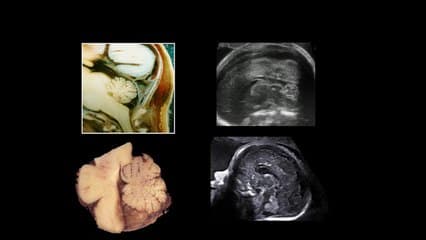

L'auteur s'attaque à la thématique. l'IRM constitue t'il le recours aux insuffisances de diagnostic des femmes enceintes obèses ? Effectivement il existe une corrélation entre le BMI et la performance de l'échographie. Il nous montre des exemples d'images convaincantes qu'il peut s'agir d'un outil complémentaire dont il sera nécessaire de poser les indications...